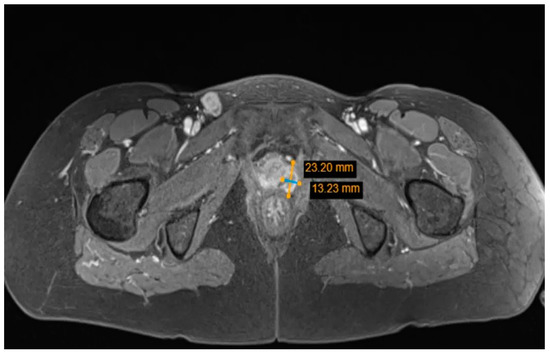

2. Case Report